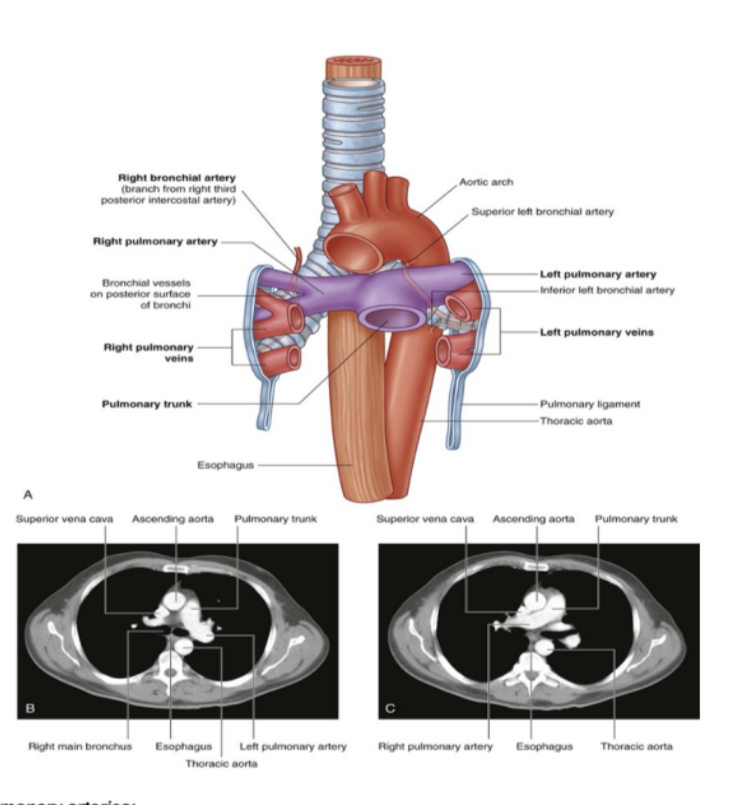

Overall vasculature of the lungs image

Pulmonary arteries (overall)

1 right, 1 left, originate from the pulmonary trunk & carry deoxygenated blood to the lungs from the right ventricle of the heart

Bifurcation of pulmonary trunk occurs to left of midline just inferior to vertebral level TIV/V, and anteroinferiorly to the left of the bifurcation of the trachea

Right vs left pulmonary arteries

Right pulmonary artery —

Slightly longer than left

Crosses horizontally at the mediastinum passes anteriorly & inferiorly to the bifurcation of the trachea, & anteriorly to the right main bronchus — also posteriorly to the ascending aorta, superior vena cava, and upper right pulmonary vein

Enters into root of lung giving off a large branch to the superior lobe of the lung

Main branch continues through hilum to give off a second recurrent branch to superior lobe before dividing to supply both the midline & inferior lobes

Left pulmonary artery —

Shorter than the right, anterior to the descending aorta & posterior to the superior pulmonary vein

Pulmonary veins —

On both sides — superior & inferior pulmonary vein

Carry oxygenated blood from lungs back to heart

Begin at hilum, pass through root of lung, & immediately drain into left atrium

Bronchial arteries

Along. with the veins form part of the nutritive system of vasculature of the lungs

Interconnect within the lung with branches of the pulmonary arteries & veins

Originate from the thoracic aorta or one of its branches —

A singular right bronchial artery normally arises from the third posterior intercostal artery

Occasionally originates from upper left bronchial artery

2 left bronchial arteries directly arise from the anterior surface of the thoracic aorta —

Superior left bronchial artery arises — vertebral level TV

Inferior left bronchial artery arises inferior to left bronchus

They run on the posterior surfaces of the bronchi & ramify in the lungs to supply pulmonary tissues

Bronchial veins —

Right bronchial vein drains into the azygos vein

Left bronchial vein drains into the accessory hemi-azygos or left superior intercostal vein

Bronchial veins also receive some blood from esophageal veins